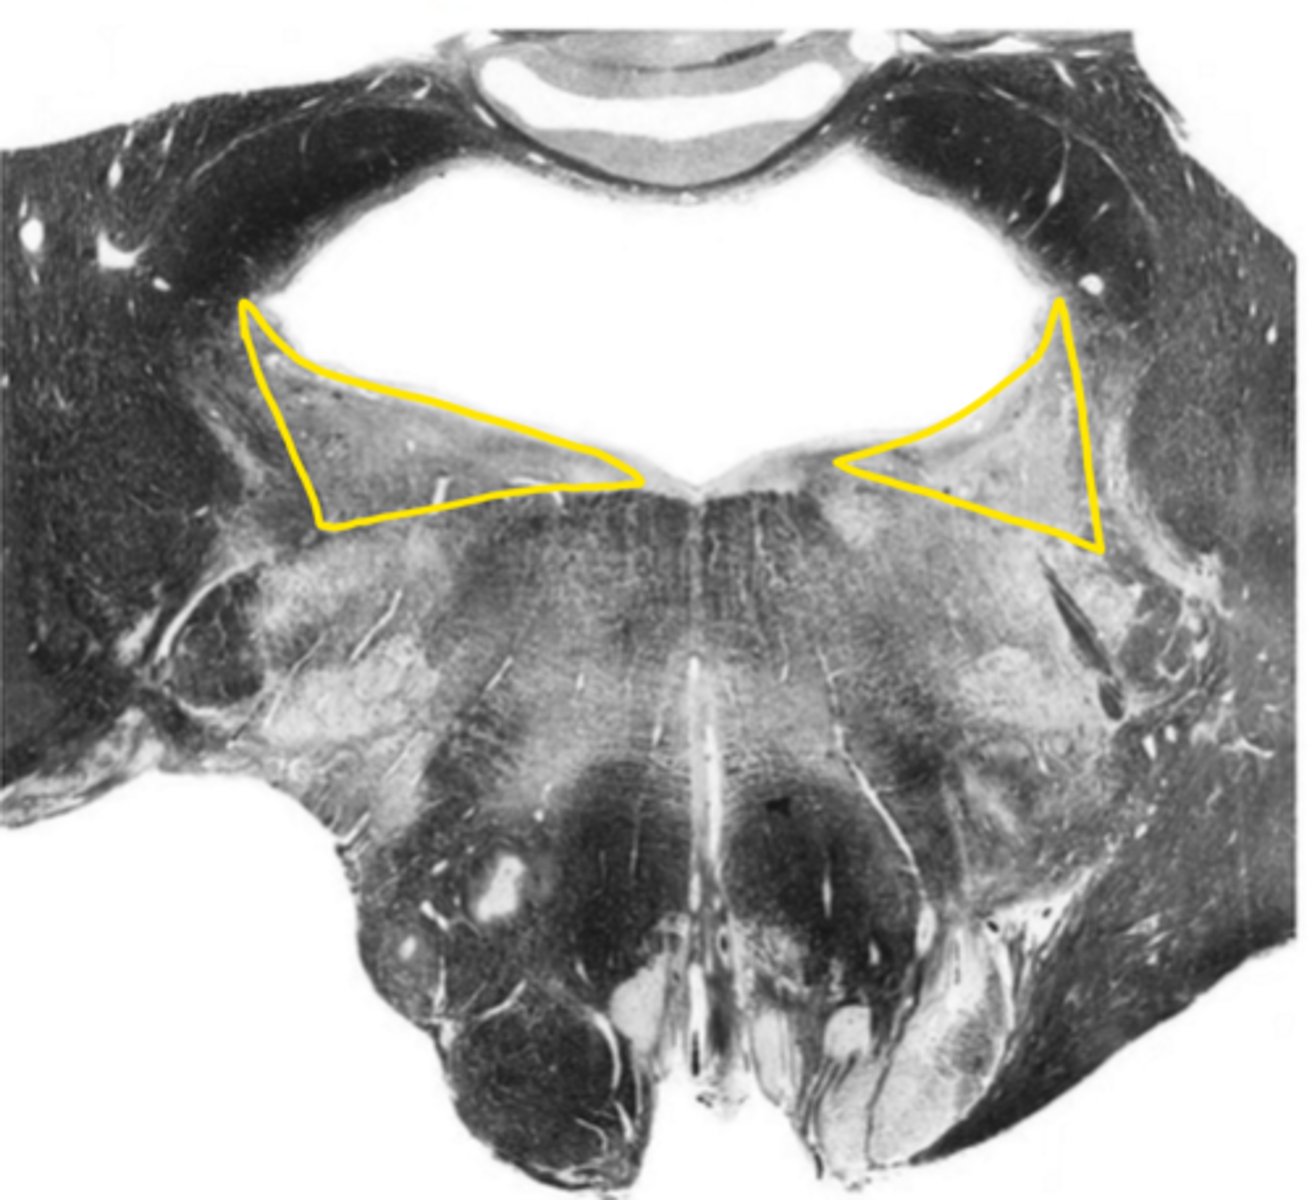

central canal

ID the space

central gray

ID the structure

hypoglossal nucleus

ID the nucleus

gracile nucleus

cuneate nucleus

inferior cerebellar peduncles

reticular formation

internal arcuate fibers

ID the fibers

principle olivary nucleus

medial lemniscus

corticospinal fibers

anterior median sulcus